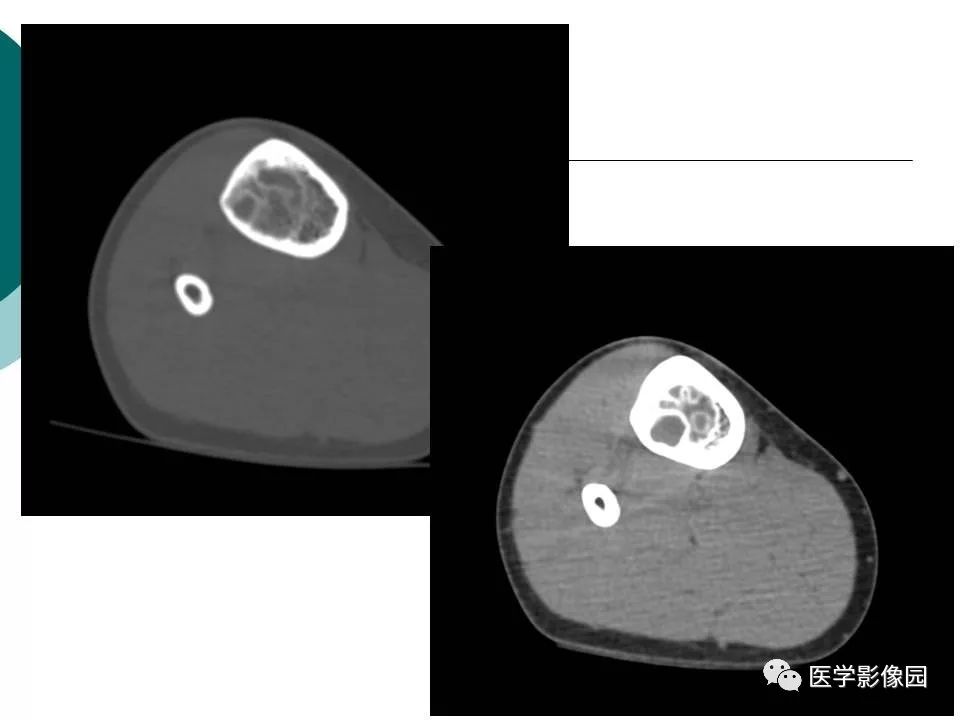

【病例】胫骨非骨化性纤维瘤1例CT及MR